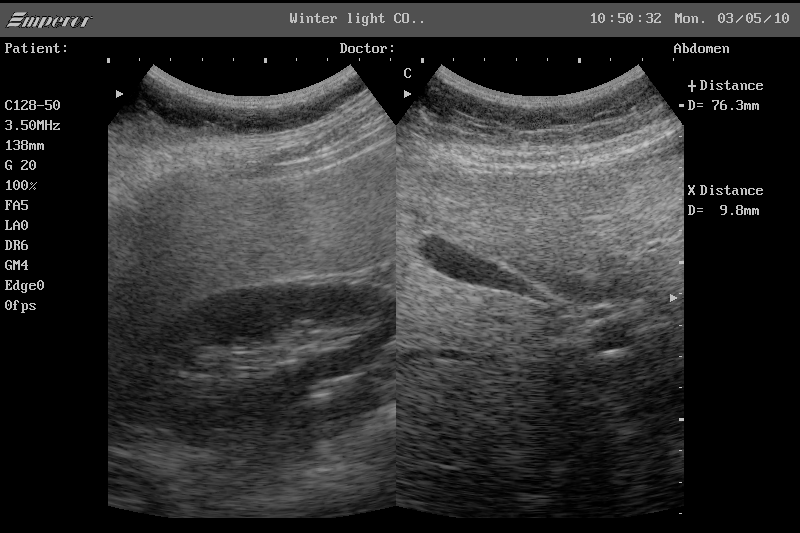

간은 복부 초음파의 핵심 관찰 대상입니다. 간 실질의 에코 패턴을 통해 지방간 여부를 비교적 정확하게 판단할 수 있으며, 지방 침착의 정도에 따라 경증, 중등도, 중증으로 나누어 추정이 가능합니다. 또한 간낭종, 간혈관종과 같은 양성 종양은 초음파에서 특징적인 모양으로 관찰되는 경우가 많아 추적 관찰 여부를 결정하는 데 도움이 됩니다. 간경변이 진행된 경우에는 간 표면이 불규칙해지고 비장이 커지는 소견이 함께 나타날 수 있으며, 이는 만성 간질환의 중요한 단서가 됩니다. 다만 간암의 경우 초기 병변은 초음파에서 놓칠 수 있어, 고위험군에서는 CT나 MRI와 병행하는 것이 일반적입니다.